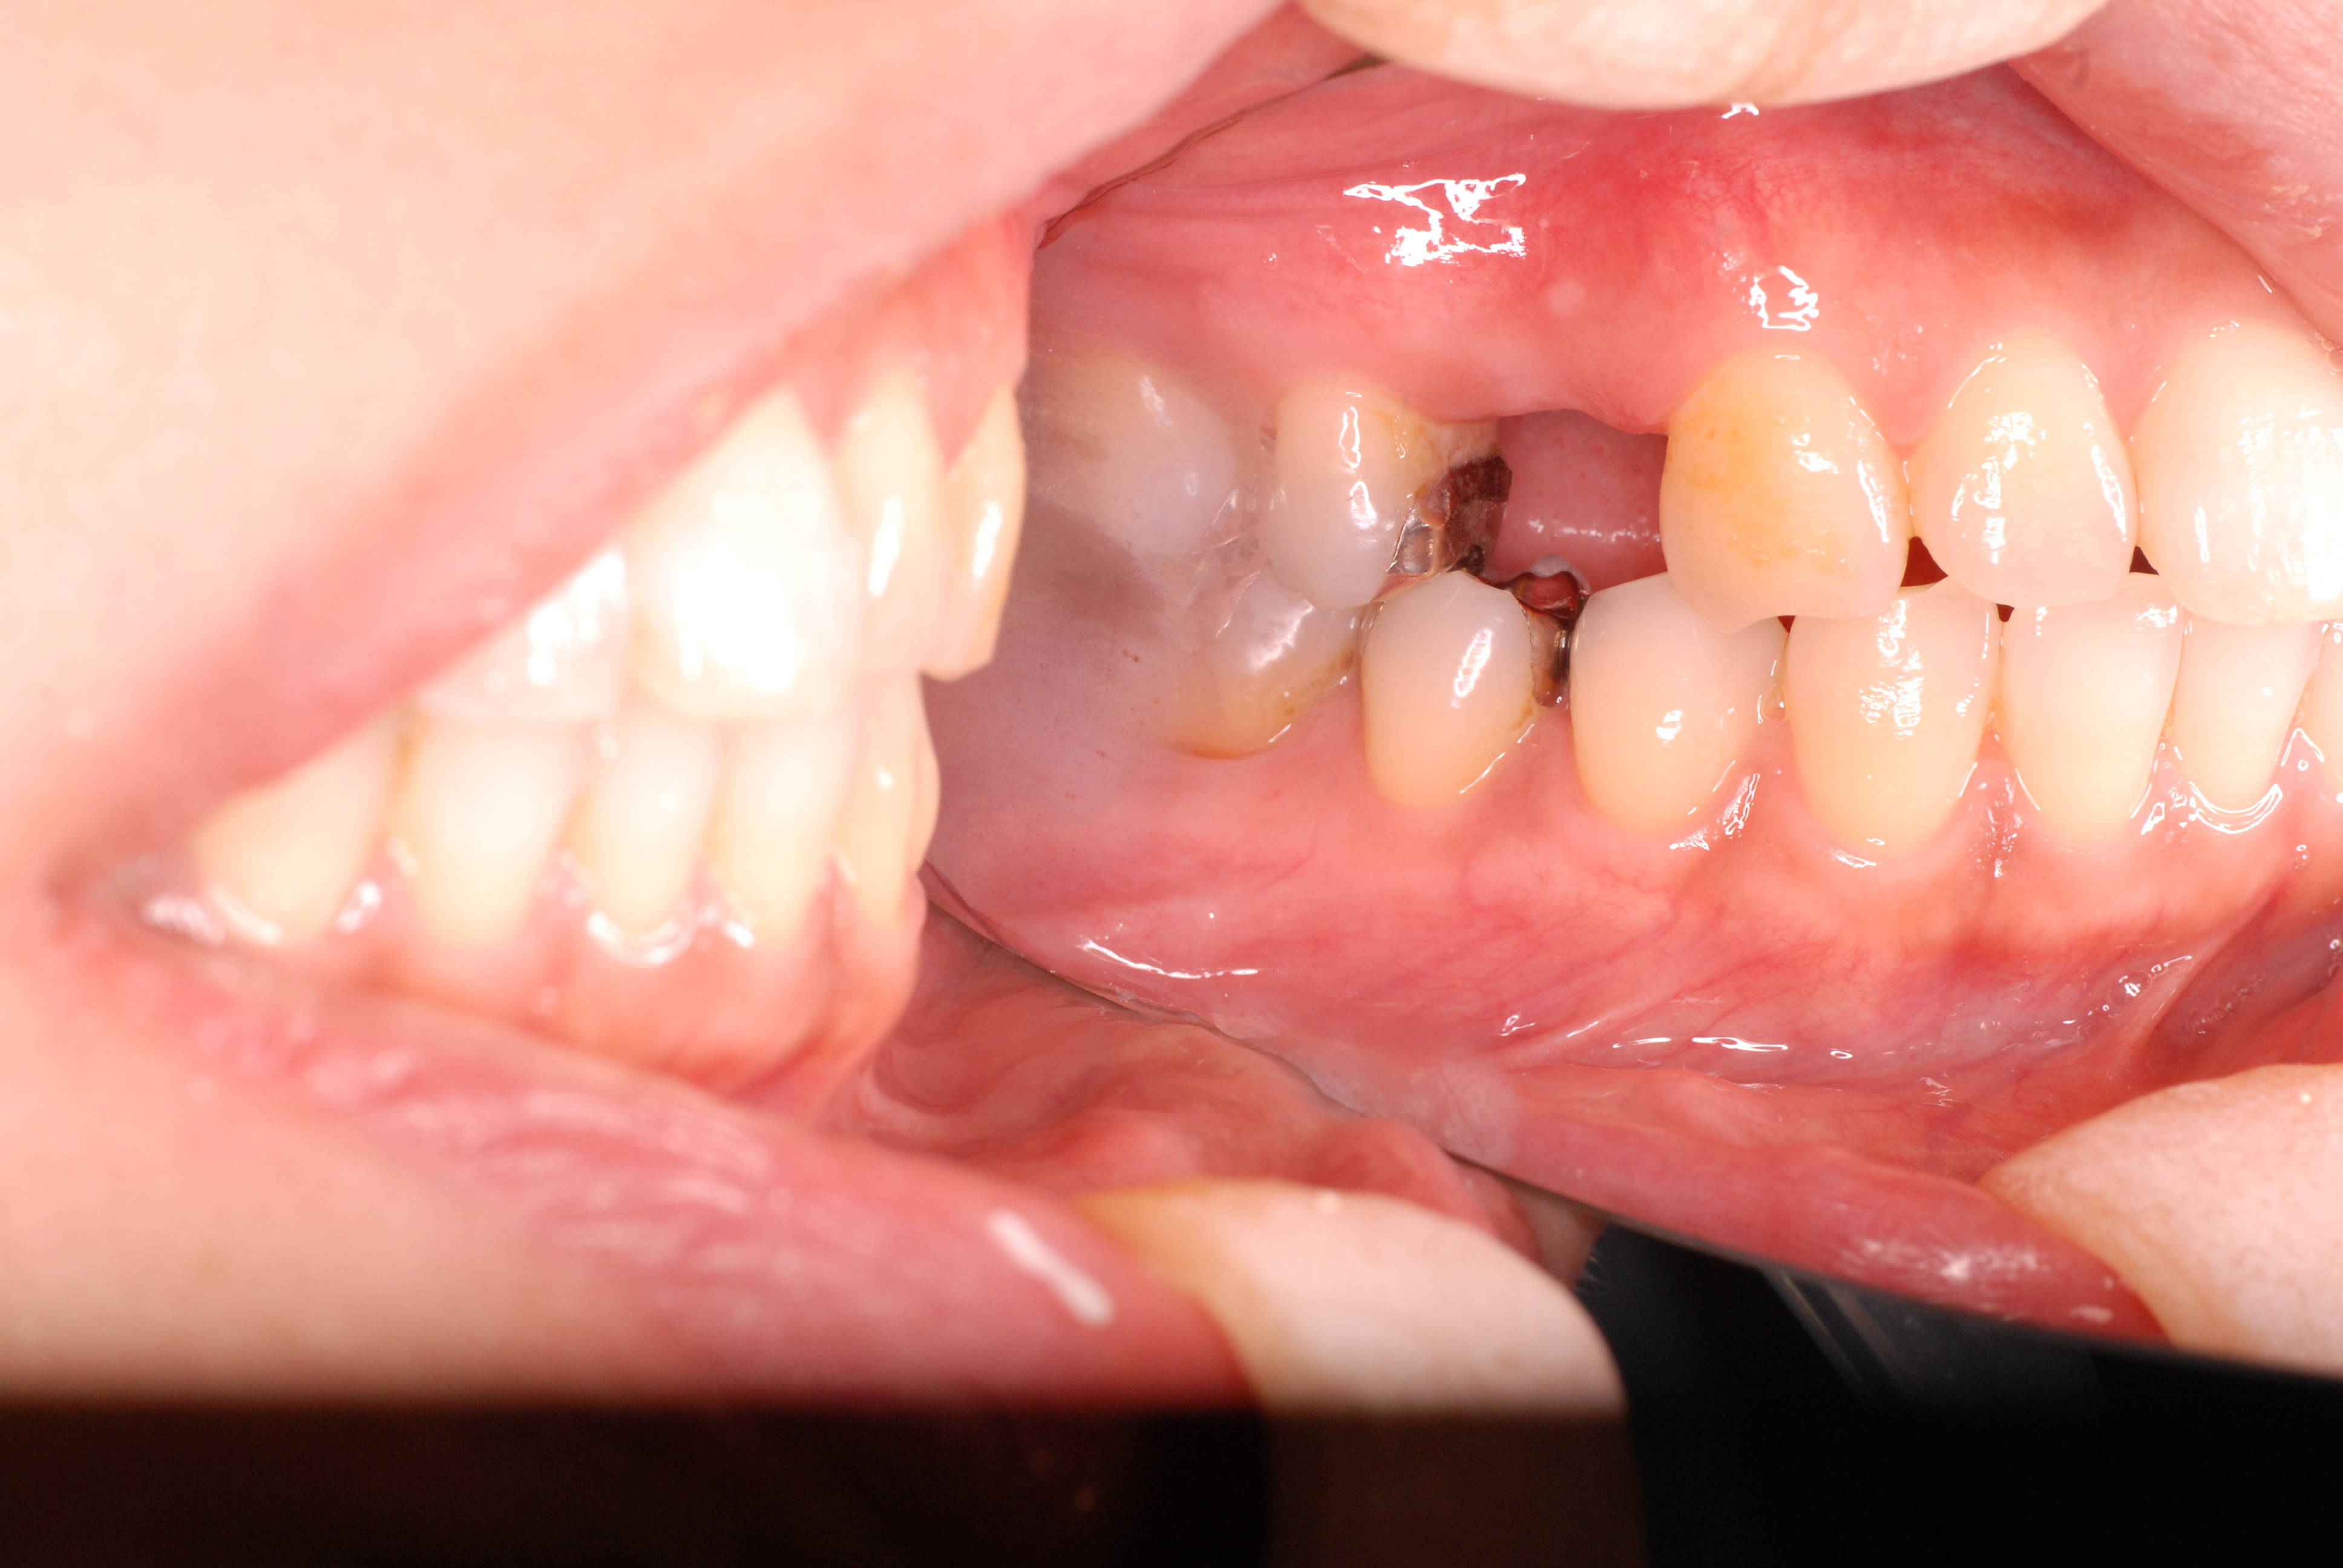

必ずばい菌が侵入しないようにしてばい菌である虫歯を除去します。

銀歯の下はばい菌だらけです。こういうのはよくあります。取り残しですね。![treatment_05[1]](https://livedoor.blogimg.jp/netdental/imgs/3/a/3ad019d0-s.jpg)